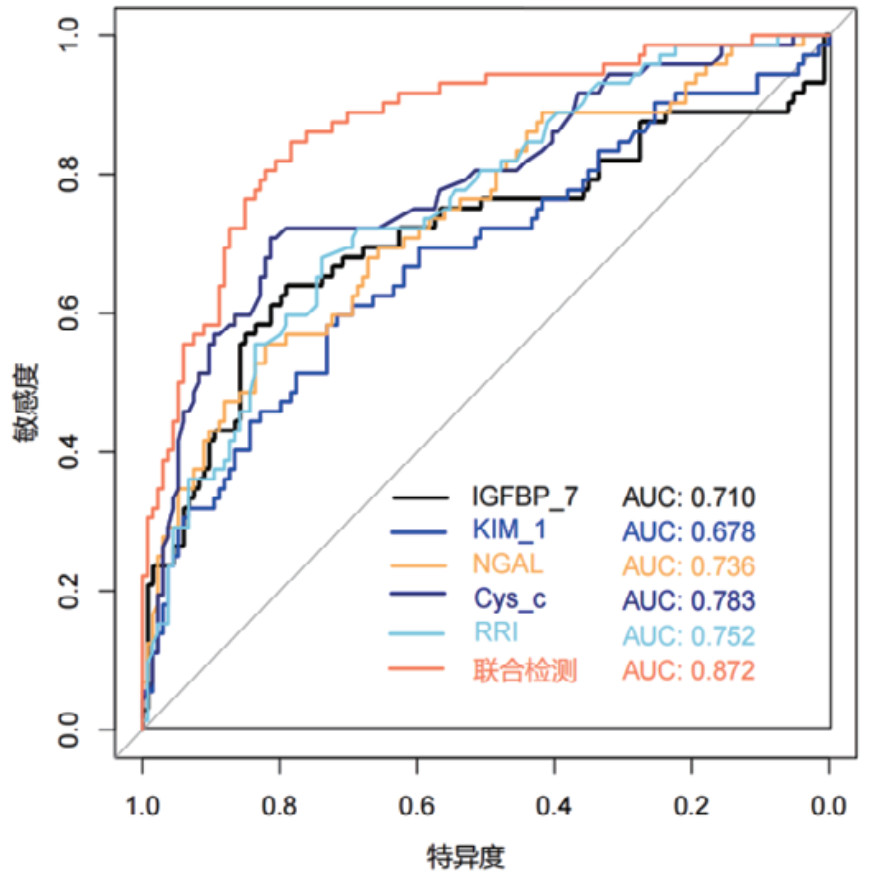

对各时间段血清Cys-C、IGFBP-7、KIM-1、NGAL和超声RRI水平及联合检测进行ROC曲线绘制,计算不同时间段联合检测的AUC值、最佳截断值、敏感度、特异度和约登指数。结果显示,联合检测0 h、12 h、24 h和48 h的AUC值分别为0.838(95%CI: 0.778~0.897)、0.852(95%CI: 0.797~0.907)、0.868(95%CI: 0.816~0.921)和0.872(95%CI: 0.820~0.924),见表 3。不同时段的AUC值提示联合检测的诊断效能要高于单项指标检测,结果见图 2、图 3、图 4和图 5。各指标各时间段的详细回归系数、标准误、P值、比值比(OR)及其95%置信区间见补充表S1。

| 检测变量 | AUC | 95%CI | 截断值 | 敏感度 | 特异度 | 约登指数 |

| 联合检测(0 h) | 0.838 | 0.778~0.897 | 0.403 | 69.44% | 82.83% | 0.523 |

| 联合检测(12 h) | 0.852 | 0.797~0.907 | 0.316 | 79.17% | 79.10% | 0.583 |

| 联合检测(24 h) | 0.868 | 0.816~0.921 | 0.309 | 81.94% | 80.60% | 0.625 |

| 联合检测(48 h) | 0.872 | 0.820~0.924 | 0.272 | 84.72% | 78.36% | 0.631 |

| 图 2 单项和联合检测0 h的ROC曲线 |

|

| 图 3 单项和联合检测12 h的ROC曲线 |

|

| 图 4 单项和联合检测24 h的ROC曲线 |

|

| 图 5 单项和联合检测48h的ROC曲线 |

由于AKI发病机制复杂多样,依靠单一标志物检测难以准确全面的反映AKI的各种变化,尽管目前已有很多研究证实了这些生物标记物存在诊断价值,但是其综合诊断效能仍难以满足临床需要,特别是在重症颅脑损伤合并早期AKI这一领域。本研究发现,单一生物标志物在诊断AKI时存在局限性,而通过联合检测可弥补不足,提高诊断的敏感度和特异度。血NGAL、Cys-C、KIM-1、IGFBP-7联合RRI可从不同角度反映肾脏损伤情况,反映肾脏损伤的多方面特征。其中,NGAL在肾小管上皮细胞受损后迅速升高,能够反映肾脏的急性损伤情况;Cys-C能通过肾小球滤过并在近曲小管重吸收,其水平变化与肾小球滤过率密切相关;KIM-1在肾小管上皮细胞受损后表达增加,能够反映肾小管的损伤程度;IGFBP-7是细胞周期阻滞因子,能促进肾小管细胞基因的整合修复,RRI指标能监测肾脏血流灌注情况,这些指标联合检测可更加全面地评估肾脏损伤的严重程度和类型。

本研究结果显示,既往存在肾脏疾病是发生AKI的危险因素,AKI患者早期SCr和BUN水平显著高于非AKI组患者,AKI组患者的eGFR指标更低。其次,AKI组患者在0 h、12 h、24 h和48 h时间段内,血清NGAL、Cys-C、KIM-1、IGFBP-7水平及超声RRI值均高于非AKI组更高。这一结果提示,该生物标志物和RRI值的变化可以作为AKI早期诊断的敏感指标。此外,RRI值的升高也反映了肾脏血管阻力的增加和肾脏血流灌注的减少,是AKI发生的重要预测因素。但是单一指标的检测存在局限性,各项指标绘制的ROC曲线AUC值相对偏低,联合检测的AUC值优于各单项指标检测,其中联合检测48 h的AUC值最高为0.872(95%CI: 0.820~0.924),且敏感度和特异度相对较高。对各时间段联合检测指标显示各时间段预测性能比较接近,AUC值均大于0.8,提示联合检测稳定性和预测性能良好。此外,对各指标随时间变化的动态监测显示,Cys-C和KIM-1呈持续上升趋势,IGFBP-7在12 h达峰值后略有下降,NGAL在早期即显著升高并维持高水平,RRI随时间推移逐渐上升。这些指标的动态监测为AKI的早期识别、严重程度评估和预后判断提供了重要依据。不同指标在时间维度上的变化特征也反映了AKI发生发展过程中不同的病理生理机制。